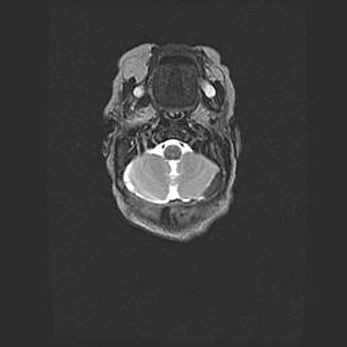

Подострая гематома правой гемисферы мозжечка.

Наружная гидроцефалия.

Возраст: 15 дней

Вес: 3100 г

Пол: женский

Окружность головы: 37 см

Срок гестации: 35-36 недель

При открытой наружной форме гидроцефалии у новорожденных расширяются и переполняются субарахноидные пространства.

Кровоизлияния в мозжечок имеют две клинико-анатомические формы: полушарные гематомы и кровоизлияния в червь.

К появлению этой патологии может привести: повреждения головного мозга, возникающие в результате асфиксии и гипоксии плода при беременности, или травмы во время родов. Редко гематома мозжечка может быть результатом первичной коагулопатии и сосудистой мальформации, диссеминированном внутрисосудистом свертывании, изоиммунной тромбоцитопении.